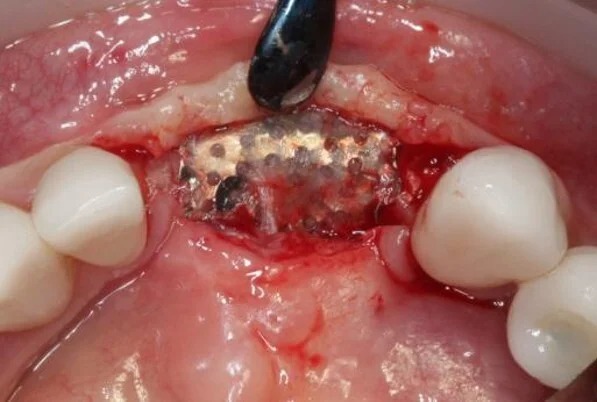

Фотографии учебного материала